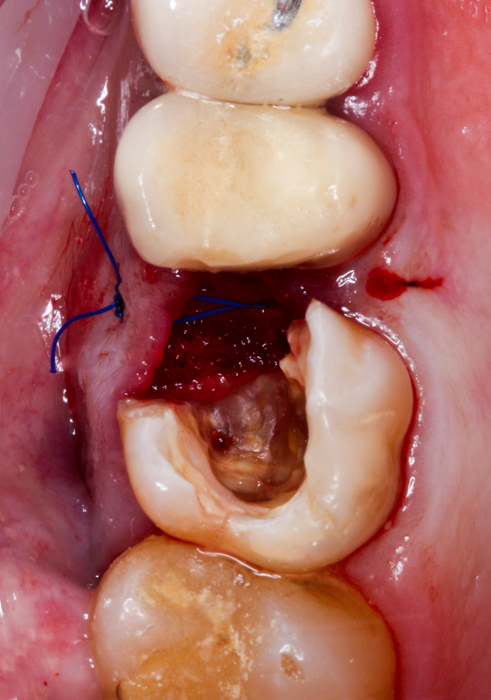

Tak właśnie było w przedstawionym poniżej przypadku – w korzeniu policzkowym bliższym zęba uprzednio leczonego kanałowo znajdował się bardzo głęboko schodzący poddziąsłowo ubytek próchnicowy, sięgający niemal brzegu kości, ponadto torbiel okołowierzchołkowa i widoczny, spowodowany być może stanem zapalnym wokół zęba, odczyn w zatoce szczękowej, manifestujący się pogrubioną błoną śluzową. Po dokładnej diagnostyce radiologicznej wspartej badaniem tomograficznym CBCT i omówieniu z pacjentem wszystkich możliwych wariantów wraz z wynikającymi z nich korzyściami i ryzykiem, wybór padł na radektomię.

W znieczuleniu miejscowym, z użyciem mikroskopu, maleńkim wiertłem odcięty został uszkodzony korzeń tak, aby w możliwie najmniejszym stopniu uszkodzić fragmenty zęba, które mają pozostać w jamie ustnej pacjenta oraz otaczającą je kość. Następnie, niezwykle ostrożnie, usunięto odpreparowany korzeń, wyłuszczono w całości torbiel i założono szew stabilizujący powstający w zębodole skrzep. Pozostałą część zęba zabezpieczono materiałem kompozytowym do czasu, gdy będzie możliwe wykonanie powtórnego leczenia kanałowego i ostateczna odbudowa części koronowej.